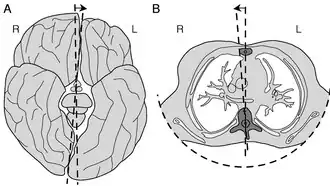

Vertebrae of the spine, especially in the thoracic region, are, on average, asymmetric.[11] The mid-axis of these vertebral bodies tends to point systematically to the right of the median body plane. A strong asymmetry of the vertebrae and their musculature, may lead to mechanical instability of the column, especially during phases of rapid growth. The asymmetry is thought to be caused by an embryological twist of the body.[51]

Scoliosis is defined as a three-dimensional deviation in the axis of a person's spine.[45][7] Most instances, including the Scoliosis Research Society, define scoliosis as a Cobb angle of more than 10° to the right or left as the examiner faces the person, i.e. in the coronal plane.[87]

Scoliosis has been described as a bio-mechanical deformity, the progression of which depends on asymmetric forces otherwise known as the Hueter–Volkmann Law.[31]